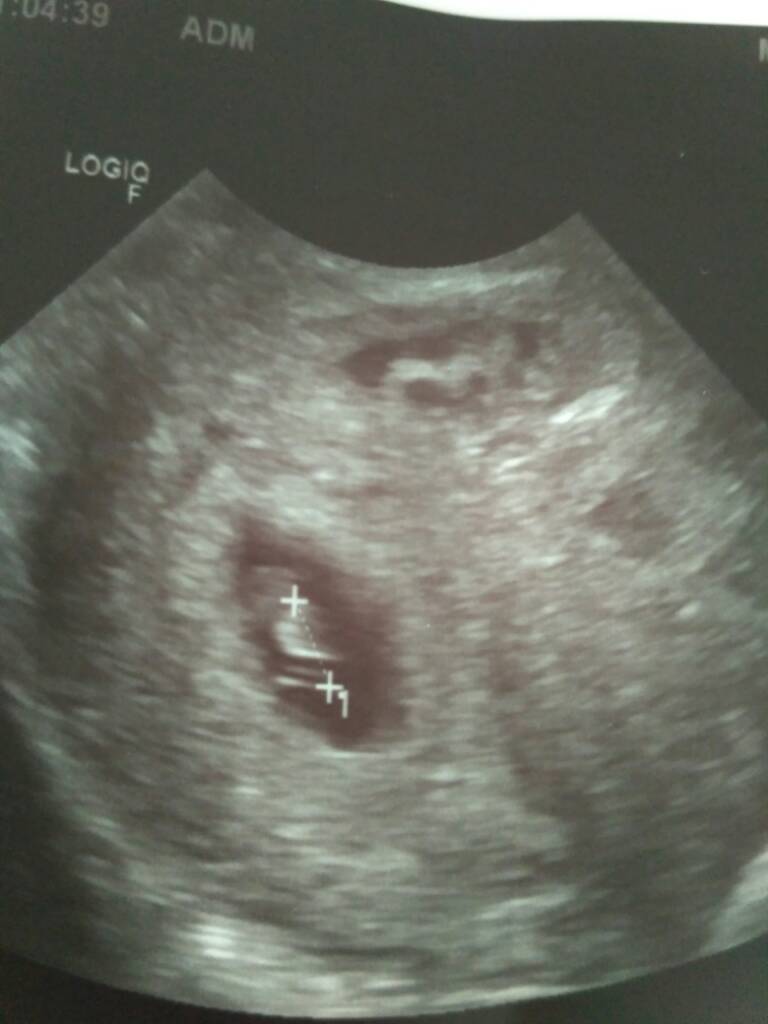

To są blizniaki, tyle że jedno jest bardzo małe 7+2 i 6+3 pytałam się czy to może się skończyć dobrze to powiedziała że tak ale że dysproporcja jest duża

Mówiła że może być zespół podkradania dlatego takie różnice ale na tym etapie to nie wiadomo za duzo

kontrola za tydzień, mam duphaston i coś tam jeszcze, zaraz przejdę do apteki kupic.